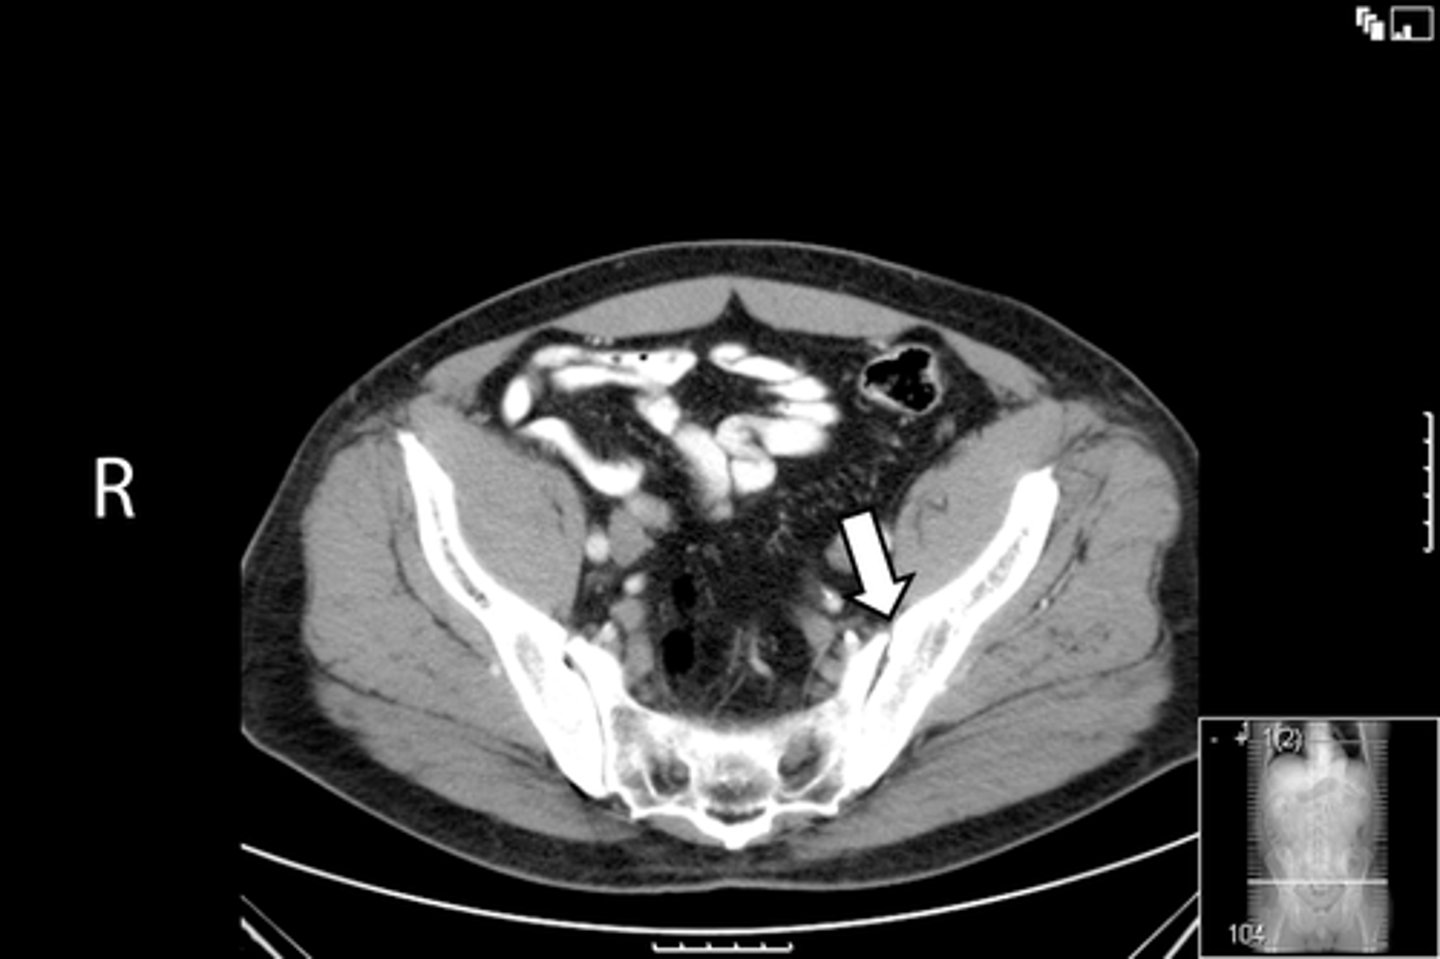

Axial male pelvis CT

What is the image?

78

Descending colon/sigmoid colon juncture

What is indicated in the image?

<p>What is indicated in the image?</p>

New cards

L external iliac artery

80

L gluteus muscle

L iliopsoas muscle

82

L internal iliac artery

Posterior aspect of L iliac bone

84

L sacroiliac joint

R common iliac artery

86

R gluteus muscle

R iliacus muscle

88

Posterior aspect of right iliac bone

R psoas muscle

90

R sacroiliac joint

R and L rectus abdominis